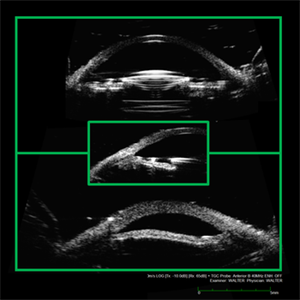

Oversized ACIOL

Apr 10 2019 by Scott D Walter, MD, MSc, FASRS

A patient with a corneal diameter of 11.5mm was implanted with an MTA4UO anterior chamber intraocular lens (ACIOL). The patient subsequently developed cystoid macular edema (CME) with petalloid angiographic leakage and secondary glaucoma. Ultrasound biomicroscopy (UBM) demonstrates appropriate centration of the ACIOL optic (top), with both haptics embedded in the anterior chamber angle (middle), and anterior bowing of the midperipheral iris (bottom). Placement of an MTA3UO lens would likely have avoided this complication.

Imaging device: Ellex 50MHz anterior B-scan probe

Condition/keywords: cystoid macular edema (CME), dislocated anterior chamber intraocular lens (ACIOL), glaucoma disorders of the lens, lrvine-Gass syndrome, uveitis glaucoma hyphaema (UGH) syndrome